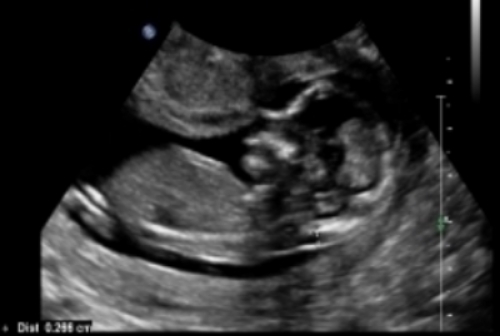

Here are some u/s pics from my friend at 13 weeks. Any nub guesses?